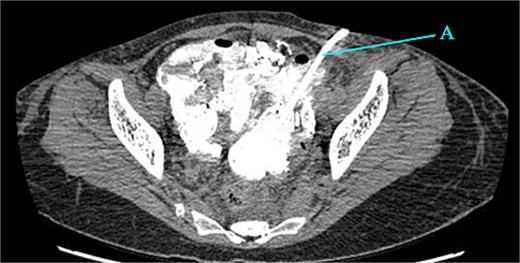

Contrast-enhanced CT of the abdomen and pelvis revealed extensive barium extravasation outlining the peritoneal cavity, accompanied by pneumoperitoneum (Fig. 3). Two barium-outlined, walled-off intra-abdominal collections were identified: one located anterior to the lower pole of the left kidney and the other in the pelvis, anterior to the rectum (Figs 4 and 5). Due to significant barium-related imaging artifacts, the precise site of bowel perforation was not identified. A diagnosis of peritonitis secondary to barium spillage was established, with associated intra-abdominal collections.

CT contrast abdomen and pelvis showing spill of barium outlining the peritoneal cavity. Stoma at the right side of the abdomen (A).